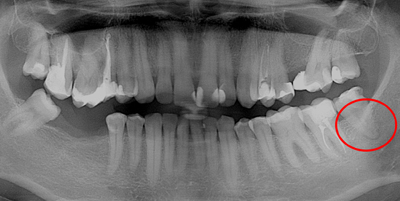

Осколок вылезать

Осколок вылезать 114 фото